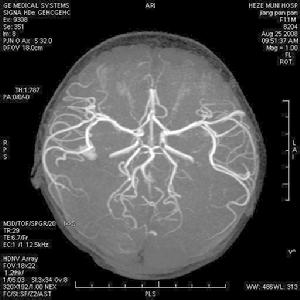

可因缺氧腦受損或死亡,據在銀行工作的母親薩拉回憶稱,當薩姆出生後僅15分鐘他就第一次停止了呼吸。據悉,通常新生兒出現呼吸問題往往是心臟有缺陷的徵兆,但檢查卻排除了這一可能性。然而蹊蹺的是,薩姆此後仍然不斷地停止呼吸。薩姆接受了相關基因缺陷檢測,並被確診患有“中樞換氣不足綜合徵”。醫生稱導致薩姆患上“中樞換氣不足綜合徵”的基因缺陷在他懷胎8個星期時就已經發生,但無人知道其中原因。據該病研究領域的頂級專家、北斯塔福德郡大學醫院兒科顧問醫生馬丁·薩繆斯介紹,“中樞換氣不足綜合徵”以前又稱“奧丁的詛咒”,通俗地講,患者由於基因缺陷導致大腦內負責控制自動呼吸的中樞神經系統出現了異常,從而無法在體內血液缺氧的時候發出信號“提醒”身體換氧,使患者“忘記”了呼吸——特別是當患者處於深度睡眠的時候。而即便患者清醒的時候,其呼吸也可能十分微弱,使得體內產生的二氧化碳廢氣無法隨呼吸及時排出,而血液內的氧氣含量也嚴重下降。這意味著,常常“忘記”了呼吸的薩姆將無法得到足夠氧氣。而一旦體內二氧化碳積累到一定程度,薩姆就可能因缺氧而導致腦部受損,甚至死亡。